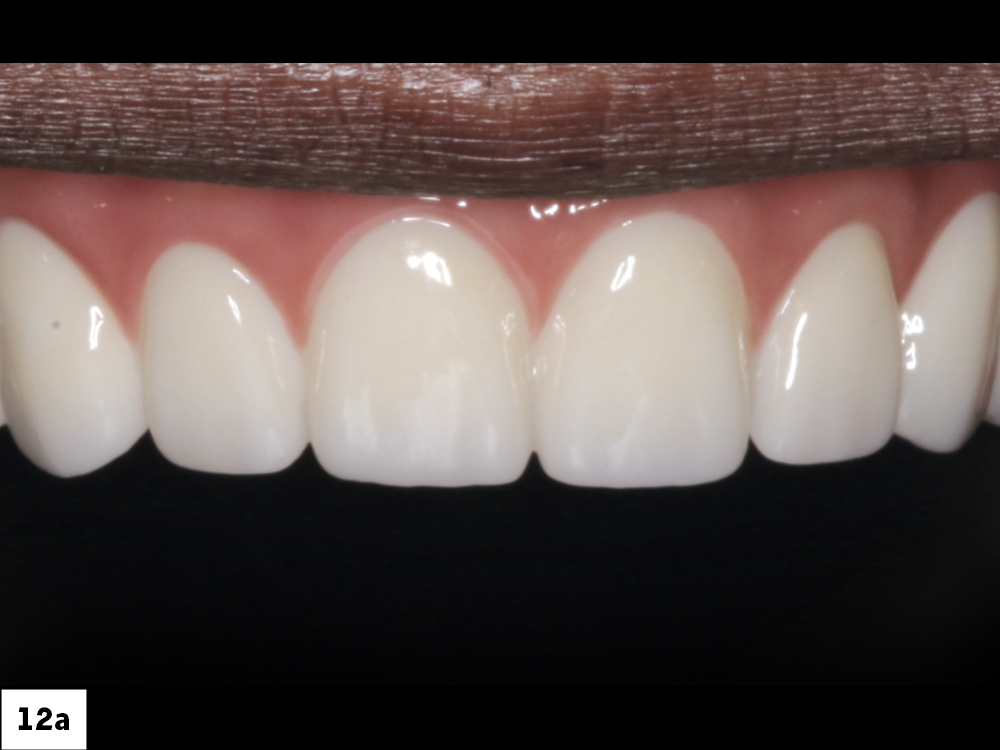

Once the first denture setups were tried in over the multi-unit abutments and approved, a polymethyl methacrylate (PMMA) provisional was milled. I then inserted this prosthesis and verified esthetics and function.

Figures 12a–12c: Once the first denture setups were tried in over the multi-unit abutments and approved, a polymethyl methacrylate (PMMA) provisional was milled. I then inserted this prosthesis and verified esthetics and function.